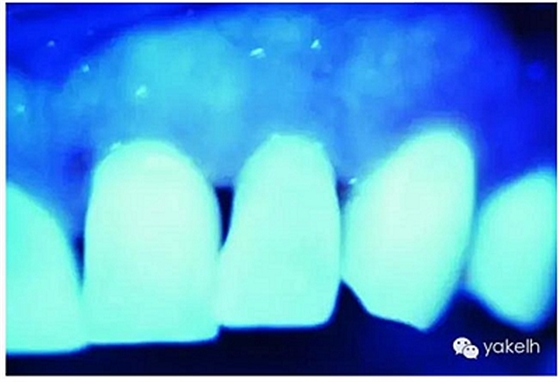

天然牙暴露在紫外線光下顯示熒光,通常是白色淡藍色的色調(藍白色)[13,22]。由于有機物的存在,以及大量有機物色素對紫外線光譜的感光性,牙本質是產生熒光的主體,比牙釉質的熒光更強烈。

有研究表明,天然牙和天然蛋白質的熒光很可能是從氨基酸苯丙氨酸結合物和酪氨酸色氨酸引起的能量轉移所導致。牙本質比牙釉質顯示出更高程度的熒光性,釉質的熒光性非常低,礦化程度的增高,導致熒光性降低。熒光隨著牙本質脫礦而增加,這解釋了為什么釉質作為高度礦化組織,相對于牙本質表現(xiàn)出非常低的熒光性的原因。

圖2.30,圖2.31通過紫外線光照下的天然牙齒,顯示牙齒的熒光性。

圖2.34紫外線光下的天然牙:釉質豐富區(qū)域,熒光的發(fā)射減少,表現(xiàn)出更強烈的藍色。